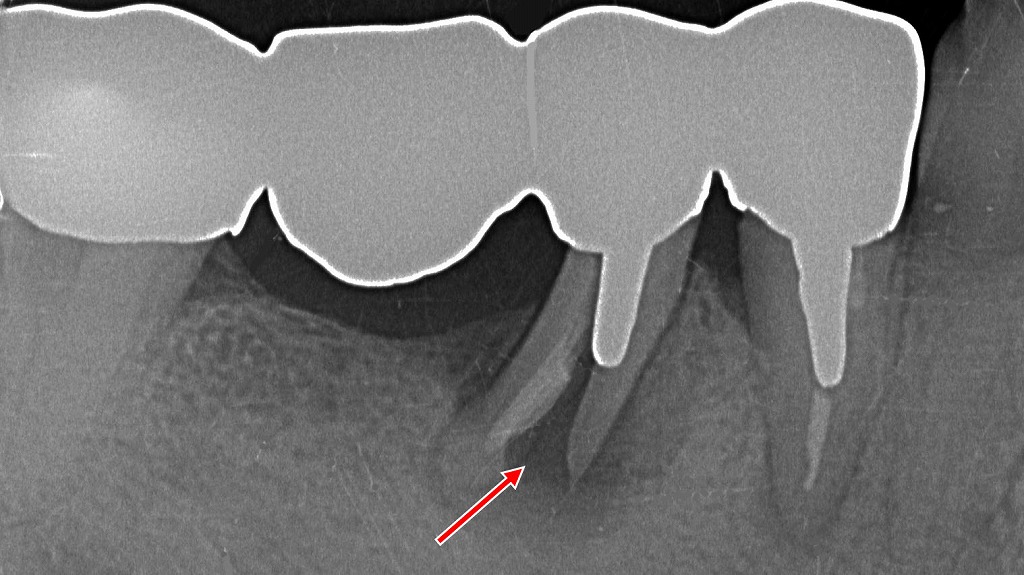

⚠️ 4・5・6・7番ブリッジ|5番支台歯に歯根破折を認める症例

4・5・6・7番に装着されたブリッジ症例です。6番はダミー(欠損部)で、支台歯である5番の歯根に破折線(矢印)が確認されます。歯根破折は保存が困難なケースが多く、ブリッジ全体の再治療や抜歯を含めた治療方針の見直しが必要となる代表的な所見です。